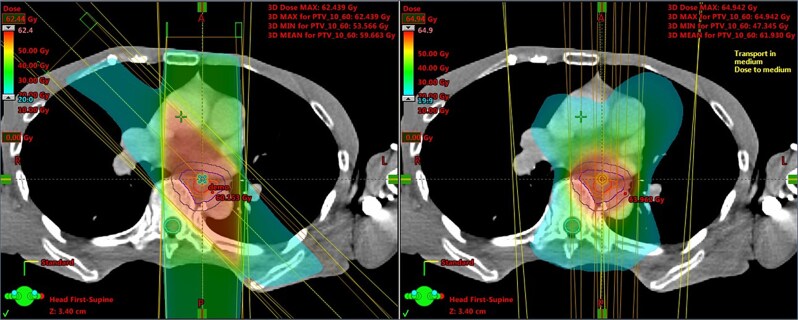

日本放射肿瘤学学会(JASTRO)放射治疗计划指南自2004年第一版出版以来,每四年修订一次,以纳入最新发现。这篇综述介绍了2024年JASTRO食管癌放疗计划指南的英文版本。关于食管癌的治疗,在过去的4年里出现了各种新的发现,导致2020年版的重大更新,特别是在以下六个方面:(i)浅表癌适应症的更多细节,(ii)日本局部晚期病例新辅助化疗和放化疗的临床试验结果(JCOG1109), (iii)预防性淋巴结照射的更新参考文献,(iv) IMRT的更新,(v)根据食管癌治疗指南第5版的修订,以及(vi)在同期化疗方案中增加FOLFOX。

The Japanese Society for Radiation Oncology (JASTRO) Guidelines for Radiotherapy Treatment Planning have been revised every four years to incorporate the latest findings since the publication of the first edition in 2004. This is a review which presents the 2024 JASTRO Guidelines for radiotherapy treatment planning for esophageal cancer in English. Regarding the treatment of esophageal cancer, various new findings have emerged over the past 4 years, leading to significant updates in the 2020 edition, particularly in the following six areas: (i) additional details on indications for superficial cancer, (ii) inclusion of clinical trial results (JCOG1109) for neoadjuvant chemotherapy and chemoradiotherapy in locally advanced cases in Japan, (iii) updated references on prophylactic lymph node irradiation, (iv) updates on IMRT, (v) revisions in accordance with the 5th edition of the Esophageal Cancer Treatment Guidelines, and (vi) additions of FOLFOX to concurrent chemotherapy regimens.